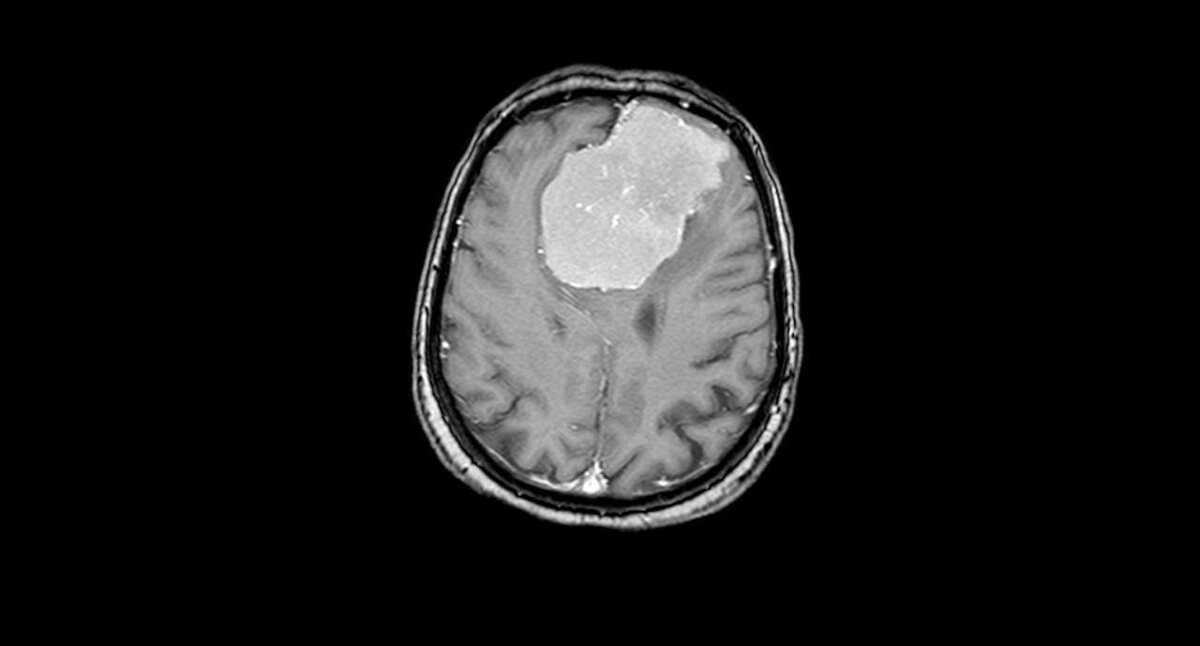

Опухоль размером с грейпфрут врачи удалили из мозга воронежской пенсионерки

В минздраве Воронежской области сообщили о героическом поступке врачей БСМП №1. В отделение нейрохирургии поступила 80-летняя пенсионерка. У нее были проблемы с речью и слабость в правой руке. Сначала медики думали, что у пожилой женщины подозрение на инсульт. Однако компьютерная томография показа, что инсульта нет. Есть опухоль в обеих долях мозга размером 6х7х8 см – с грейпфрут.

Новообразование окутывало переднюю мозговую артерию, а также прорастало в переднюю треть сагиттального синуса (один из наиболее крупных венозных коллекторов головного мозга) и закрывала его.